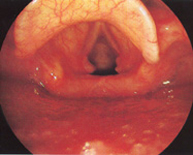

Colomé Calafí MaríaOtorrinolaringología